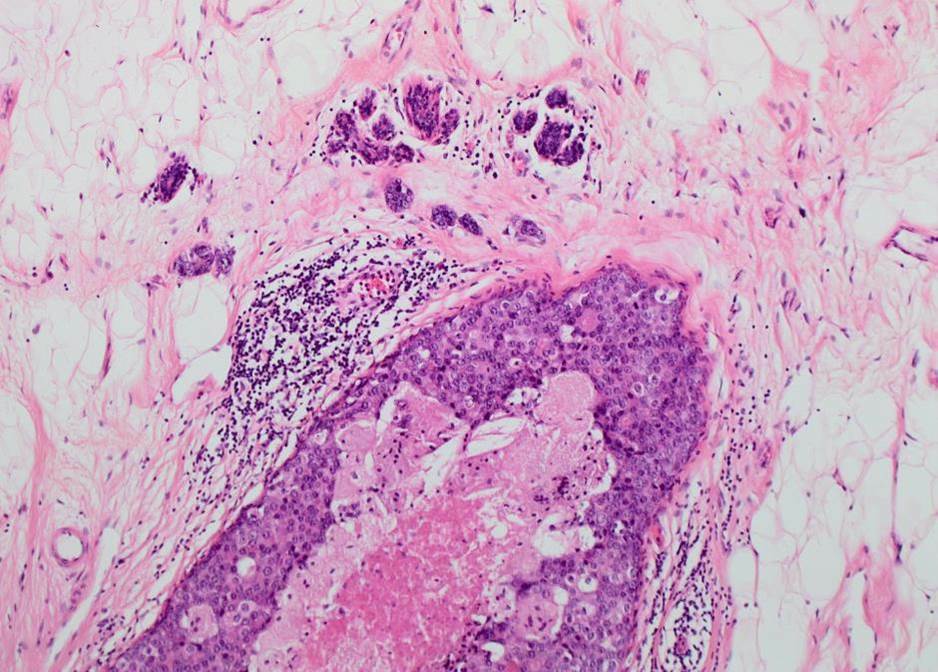

Microinvasive carcinoma is a small (< or = to 1 mm) focus of invasion usually occurring in the setting of high-grade DCIS. It is not clear, however, whether it behaves clinically as in situ or invasive disease. Due to its rarity, it has been challenging to assemble a well-characterised cohort of the lesion with long follow up.

Microinvasive carcinoma was identified in 512 of a total of 11285 patients (4.6%). The incidence, however, varied considerably among units suggesting variation in diagnosis histopathologically. It was associated with high grade DCIS, solid and cribriform patterns and comedo-type necrosis. Patients were more likely to undergo mastectomy, have axillary surgery and also to receive radiotherapy after breast conservation compared with pure DCIS. The nodal metastasis rate was not statistically different between those with pure DCIS and those women with microinvasion. Subsequent events were few, with only 4.2% of patients developing ‘true’ invasive carcinoma (i.e. >1mm in size). Breast cancer specific mortality was, however, significantly higher in women with microinvasion at diagnosis.

Microinvasive carcinoma appears more clinically aggressive than pure DCIS. Accurate diagnosis by pathologists is therefore essential. A practical tip is to examine H&E levels to assess more accurately the size of the invasive focus, since true invasion may be identified on deeper levels.  A multidisciplinary, patient-centred, management approach will help tailor treatment for individual patients.